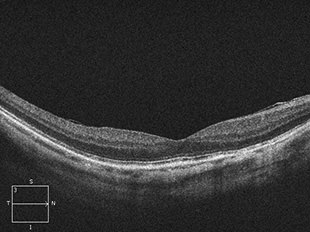

網膜静脈閉塞症

網膜静脈閉塞症は、網膜の静脈が詰まった状態で発症します。網膜の静脈が詰まると静脈の圧力が上がり、網膜の血管が広がったり、蛇行したり、出血したりします。また、網膜に血液中の水分がたまり黄斑付近に発症すると黄斑浮腫を起こします。

詰まった静脈の場所により、網膜中心静脈閉塞症、網膜静脈分枝閉塞症などに分類されます。

網膜の静脈が詰まってしまうため、網膜に出血や浮腫が起こります。そのため、ものが見えにくくなる、見えない部分があるなどの症状が出ます。特に黄斑部分に出血や浮腫ができると、視力が急に下がったり、かすんだり、黒く見えたり、歪んで見えたりします。

治療前

治療後

治療前 OCT

治療後 OCT